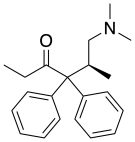

Amidones

Structures

| Amidones | ||||

|---|---|---|---|---|

|

|

|

Levoisomethadone Levoisomethadone | |

Noracetylmethadol Noracetylmethadol |

Levomethadone Levomethadone |

Methadone Methadone |

Methadone intermediate Methadone intermediate | |

Normethadone Normethadone |

Norpipanone Norpipanone |

Phenadoxone Phenadoxone |

Pipidone Pipidone | |